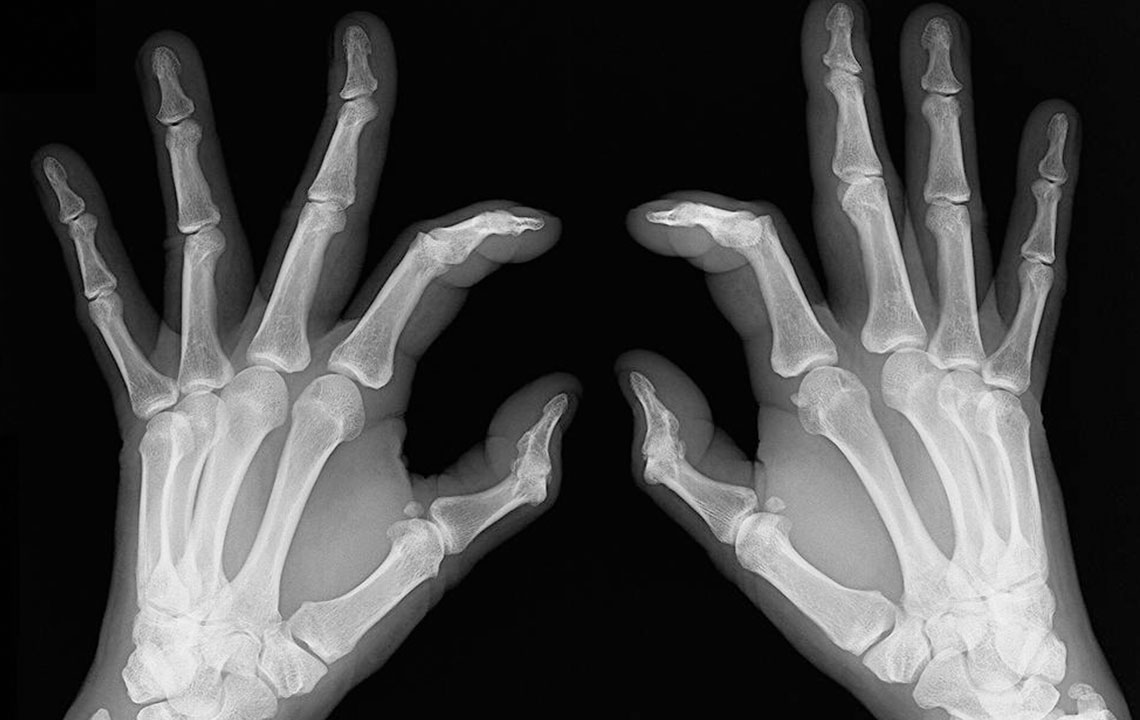

Early signs of rheumatoid arthritis and how to catch them

Rheumatoid arthritis causes chronic inflammation of joints, which results in joint pains, inflammation and bone deformation. It usually starts slowly with pain in some parts of the body that can come and go in the beginning and then spread within weeks or months. It is better in this day and age to always be aware of your health problems and not to ignore slightest of joint pains. The symptoms can vary from one person to another. Here are the many rheumatoid arthritis symptoms that you can check out.

People who have rheumatoid arthritis often wake-up early in the morning complaining of stiff joints and restricted movement. The mobility is back slowly and with little joint movements . Joint redness: Sometimes the troubled area also experiences redness and feels warm to the touch. However, make sure the redness is not due to reasons such as a bruise or a scrape of the skin. Bone deformation: Arthritis also attacks the bones and makes them crooked and stiff. Look out for signs of any subtle changes in your joints and test them for pain levels.